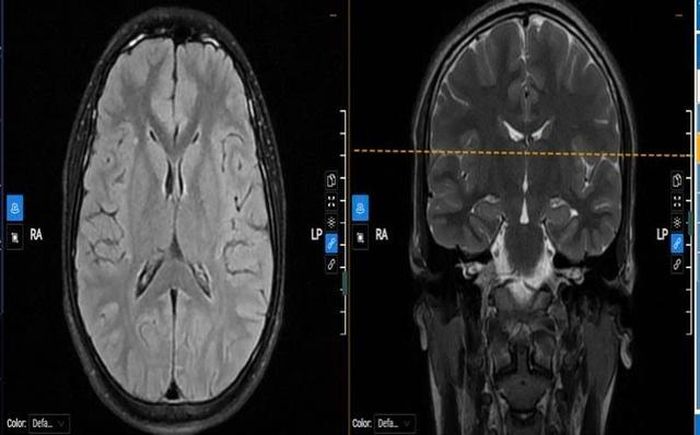

Tại MEDLATEC, kết quả điện não đồ ghi nhận hoạt động kịch phát trong dải tần số Theta, ưu thế bán cầu phải, có xu hướng lan tỏa sang cả hai bán cầu. Cộng hưởng từ não phát hiện vài nốt mất myelin rải rác tại đại não, trong khi các chỉ số xét nghiệm và thăm dò tim mạch không phát hiện bất thường nguy hiểm.

Hình ảnh cộng hưởng từ của bệnh nhân phát hiện vài nốt mất myelin rải rác tại đại não - Ảnh: BVCC.

Từ những kết quả này, các bác sĩ chẩn đoán M. mắc động kinh khởi phát cục bộ chuyển thành co cứng, co giật hai bên, đồng thời kê thuốc chống co giật điều trị ngoại trú, khuyến cáo gia đình theo dõi sát và hạn chế các hoạt động tiềm ẩn nguy cơ tai nạn.